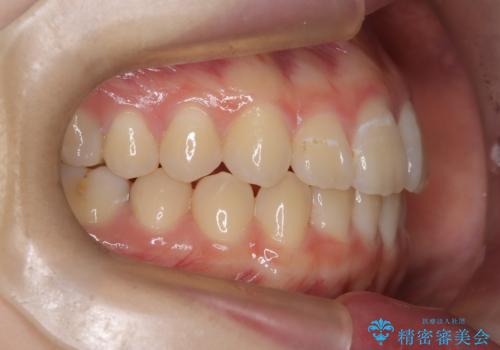

マウスピース矯正で前歯のガタツキを改善! 短期間で治療完了

- 前歯のガタツキが気になるとのことで来院されました。

前歯のガタツキに加え、奥歯の噛み合わせにも問題があったため、マウスピース矯正で治療し改善しました。